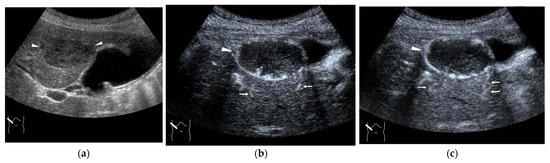

3.1. Hepatocellular Carcinoma (HCC)

3.2. Liver Metastasis

3.3. Benign Liver Tumors